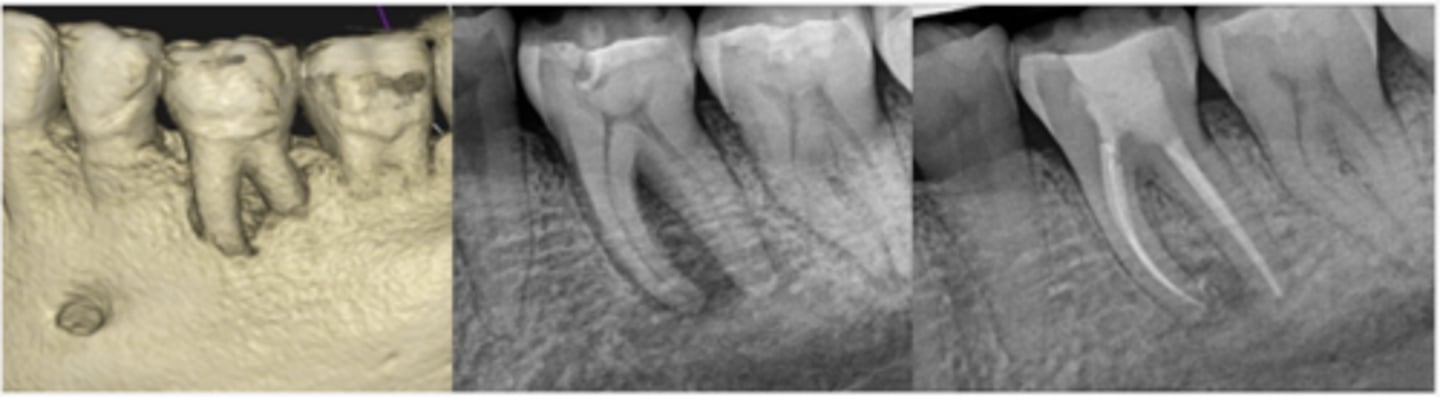

What type of lesion?

Furcation involvement and loss of buccal plate extending apically on tooth #19, visible in CBCT rendering (left) and pre-op PA radiograph (center)

Endodontic treatment was initiated and calcium hydroxide medication was placed

Four months later, tooth was obturated and healing of furcal bone was evident radiographically (right)

Primary endo with secondary perio lesions